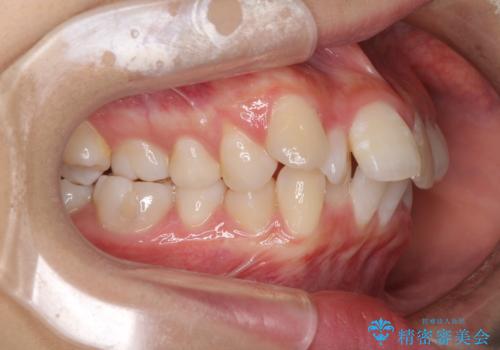

- 出っ歯とデコボコを気にして来院された患者様です。

口元の突出感を改善するため、上下左右第一小臼歯4本の抜歯を行い、ワイヤー装置による矯正治療を行うこととしました。

治療前の上下正中はずれていましたが、骨格的な上下左右差はあまり認められなかったため、正中を揃えて治療を終えることができました。